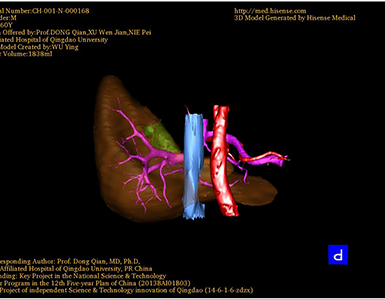

CT结果输入海信CAS系统后行3D重建及手术规划后,于2016-8-03全麻下行“脾切除术”手术治疗:

术前三维重建及手术方案设计:

将0.625mm双源薄层CT资料的静脉期和动脉期Dicom格式文件导入海信CAS系统。

通过调节窗宽窗位调整CT序号,对肿瘤,肝实质,胆囊,下腔静脉,肿瘤,肝动脉、门静脉及肝静脉等进行三维重建;系统自动计算肿瘤体积和肝脏体积。

术前手术方案的规划。

术前三维重建:

重建图片